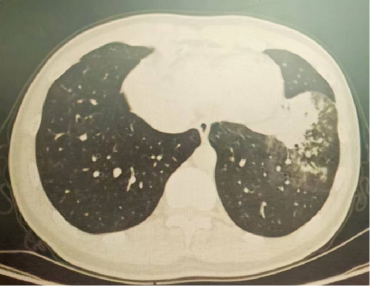

以上是他的胸部CT影像,主要表现为左下肺炎症,片絮影+磨玻璃影。

肺部感染的影像学特征

多发性结节伴快速进展

CT表现为双肺多发实性结节(直径0.5-3cm),结节边缘可见毛刺征及分叶征,特征性表现为短期内体积呈几何级数增长(如1周内增大10倍),需与转移瘤、结核球等鉴别。

混合性密度影与胸腔积液

40%病例出现磨玻璃影与实变影共存,部分结节中央可见液化坏死;30%伴单侧渗出性胸腔积液,积液分析呈渗出性但培养阴性,此表现易误诊为脓胸。

明确诊断后我们给予了正规治疗,患者咳嗽症状迅速缓解,1月后复查胸部CT提示肺部病变大部分吸收。

4月后再次复查胸部CT,提示病灶已经完全吸收。